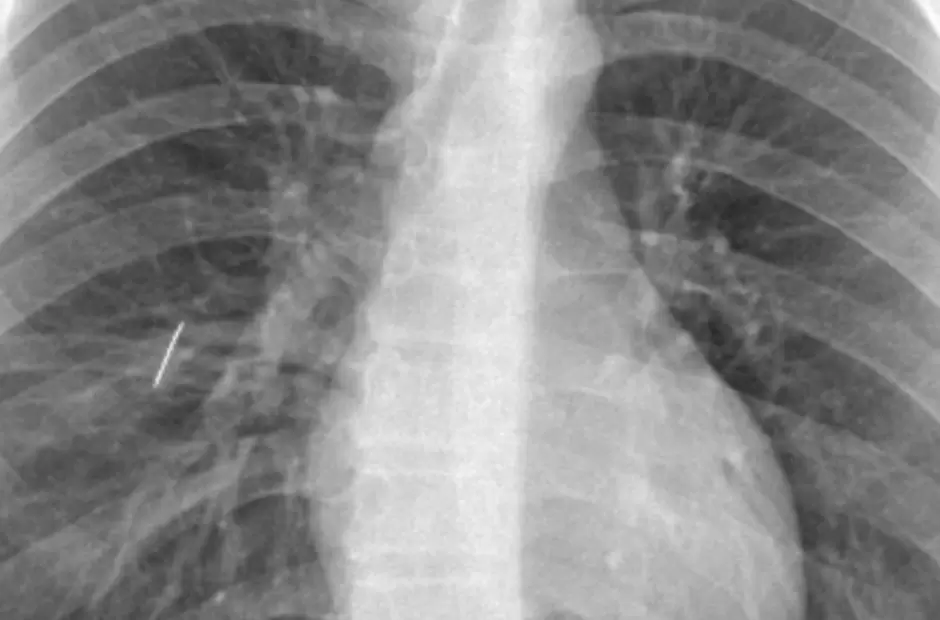

En una cirugía de alta complejidad, el Servicio de Cirugía General del Hospital Interzonal San Juan Bautista llevó adelante una intervención compleja e inédita para extraer una aguja de coser alojada en el pulmón de un paciente de 16 años, oriundo de Tinogasta, que había ingresado por guardia luego de sufrir un accidente doméstico.

El episodio se produjo cuando el joven se apoyó sobre una caja que contenía un objeto metálico, situación que le provocó un trauma penetrante de tórax. Tras una primera atención en su lugar de origen, el paciente fue derivado al hospital de referencia, donde los estudios confirmaron la presencia del cuerpo extraño dentro del pulmón.

Sin embargo, el pulmón no lograba expandirse debido a la presencia de la aguja, lo que obligó a avanzar rápidamente hacia la planificación de la resolución quirúrgica.

La complejidad del caso estaba determinada por la localización precisa del objeto y por el riesgo vital que implicaba mantenerlo en el tejido pulmonar. En ese contexto, el equipo médico definió una estrategia de abordaje que permitiera actuar de forma directa sobre el órgano comprometido.

El propio Dr. Lestussi explicó el cuadro en términos precisos: "Se trató de un trauma penetrante de tórax con un objeto metálico que resultó ser una aguja de coser, clavada en el pulmón. Era un caso que no podía derivarse por el riesgo que implicaba el traslado, por lo que la resolución debía hacerse en nuestro hospital, y con mucha satisfacción podemos decir que lo realizamos profesionales del hospital".